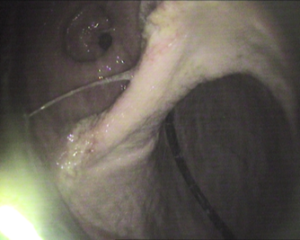

Pylorus